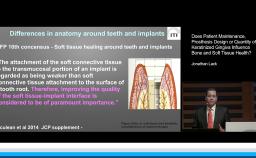

Long-term success in implant dentistry is based on the primary outcome of an implant-prosthetic complex taken as a whole. This presentation addresses current trends and scientific evidence on risk assessment, treatment planning, and implant prosthodontic considerations as indicators of treatment success. In particular, the most frequently used criteria to define treatment success for implant rehabilitations are updated. These include implant level, peri-implant soft tissue, prosthodontics, and patient satisfaction parameters. Additionally, the potential of digital dental technology to improve the accuracy of care delivery according to a specified treatment plan and to reduce complications is presented as a factor for ensuring long-term outcomes.